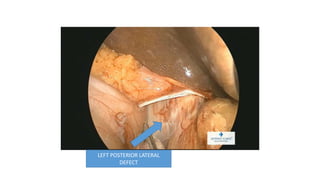

LEFT POSTERIOR LATERAL

DEFECT

CONTENTS ADHERANT TO THE SAC

EXPOSURE OF THE HIATUS

DEFECT CLOSURE

MESH PLACEMENT

Left Posterolateral Defect In Adult

DEFECT CLOSURE AND MESH PLACEMENT